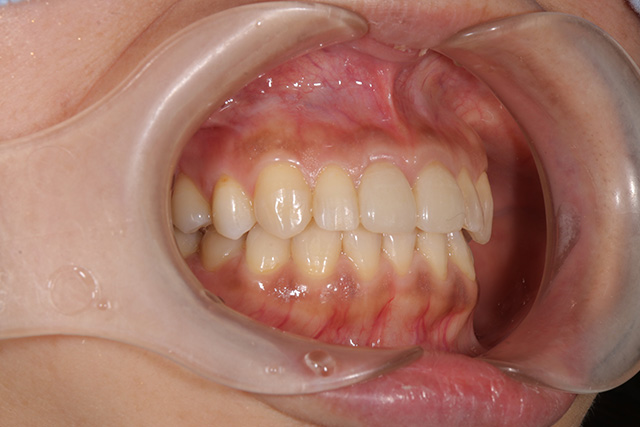

審美症例